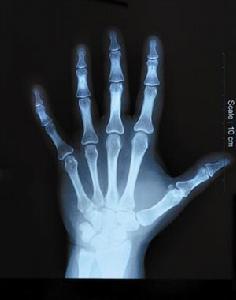

手骨骼